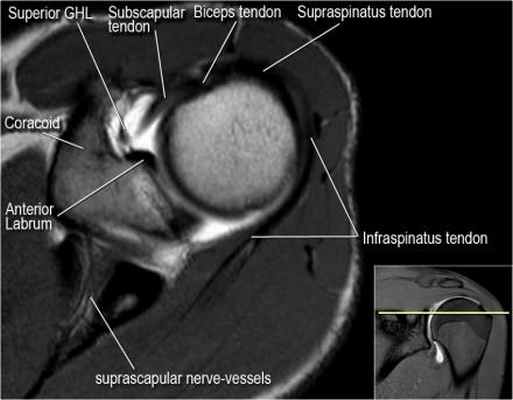

Изображение передних отделов плечевого сустава.

Сухожилие подлопаточной мышцы прикрепляется как к малому бугорку, так и к большому бугорку, давая поддержку длинной головке двуглавой мышцы в борозде двуглавой мышцы. Вывих длинной головки двуглавой мышцы плеча неизбежно приведет к разрыву части подлопаточной сухожилия. Манжета вращателей плеча состоит из сухожилий подлопаточной, надостной, подостная и малой круглой мышц.

Нормальная анатомия плечевого сустава в аксиальных изображениях и контрольный список.

- обратите внимание на верхние отделы суставной губы и прикрепление верхней плече-лопаточной связки. На данном уровне ищется SLAP-повреждение (Superior Labrum Anterior to Posterior) и варианты строения в виде отверстия под сутавной губой (sublabral foramen - подгубное отверстие). На этом же уровне по задне-боковой поверхности головки плечевой кости визуализируются повреждение Хилл-Сакса.

- волокна сухожилия подлопаточной мышцы, создавая бицепитальную борозду, удерживают сухожилие длинной головки двуглавой мышцы. Изучите хрящи.